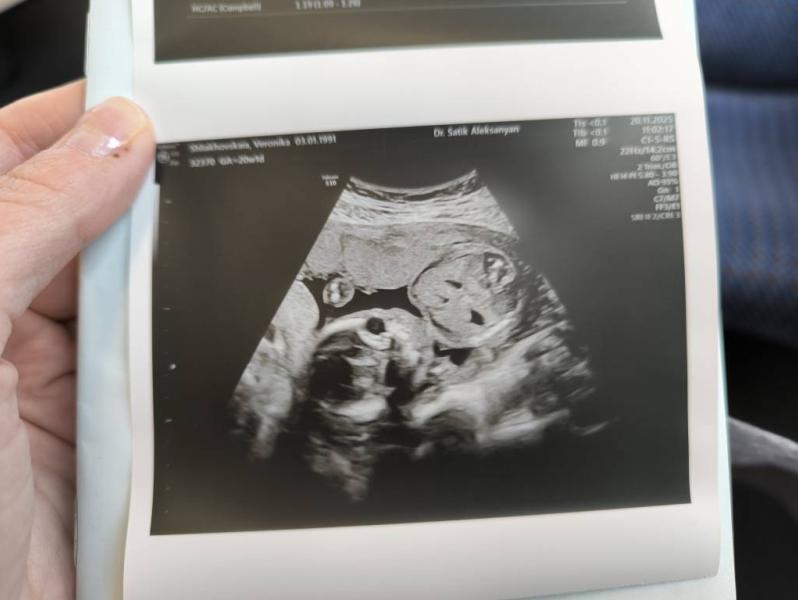

Вышла со второго скрининга. Неделю назад с мужем были на платном. Хотелось показать ему малышку на УЗИ, а сегодня была на бесплатном.

Вес малышки в 19н2д - 271г

Вес малышки в 20н1д - 360г

Шейка матки - 43 мм

ПДР по месячным - 09.04.2026

ПДР по скринингу - 03.04.2026